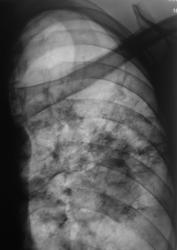

Диссеминированный туберкулёз лёгких.

Милиарная диссеминация, преимущественно в средних и нижних отделах.

Случай представлен доктором Коробейниковым.